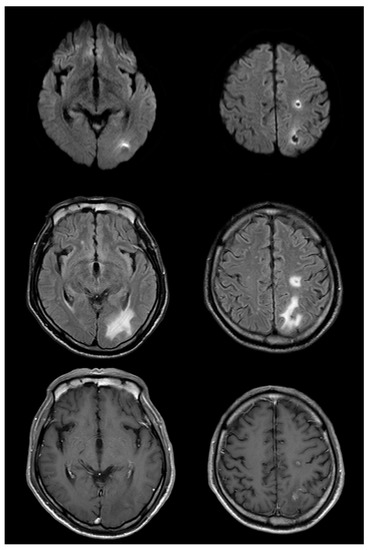

Figure 1.

Brain MRI was performed 2 days after symptom onset. (A): diffusion-weighted magnetic resonance imaging (MRI); (B): apparent diffusion coefficient map (ADC); (C): contrast enhanced T1-weighted MRI; (D): T2 *-weighted MRI; (E): fluid-attenuated inversion recovery (FLAIR); (F): T2-weighted MRI). Multiple lesions can be seen in the border area between the middle cerebral artery and posterior cerebral artery in the left hemisphere. High signal intensity lesions on diffusion-weighted MRI and their corresponding low-signal lesions on the ADC, without enhancement on contrast-enhanced T1-weighted MRI and without low signal on T2 *-weighted MRI, are seen. T2-weighted MRI shows a high signal lesion with subtle low signal in the center of the ovoid-shaped dominant peripheral lesion. Figures in the right column are magnified regions of interest from the images of the lesion marked (*).